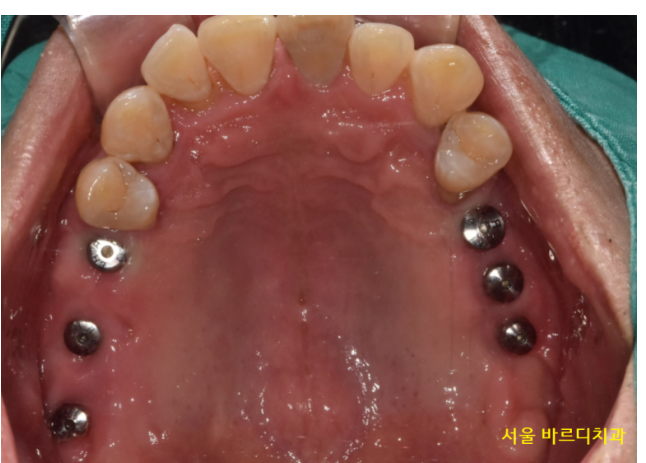

230327

그래서 그런가 입안 상태도 좋지 못했습니다.

정상적인 치아가 없을정도였죠.

안 흔들리는 치아가 없었습니다.

윗니는 개수로만 4개 없음

아랫니는 2개 없음

앞으로 뽑아야하는 치아들

230612

환자분처럼 양쪽 어금니가 다 없고

임플란트 뼈이식을 많이 해야할경우

안전하게 오른쪽 왼쪽 나눠서

임플란트 수술을 진행합니다.

환자분은 왼쪽이 많이 불편하시다 하셔서

왼쪽부터 수술을 진행하였습니다.